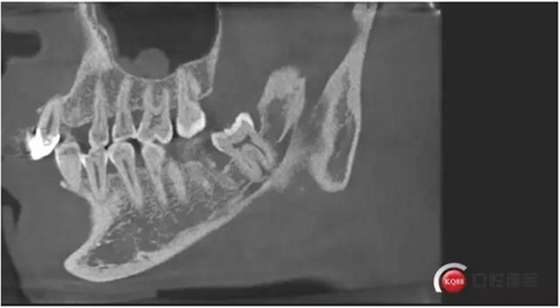

下面CBCT,可以看到兩個(gè)牙根的根尖三分之一在神經(jīng)管里面。

下面?zhèn)惹忻?p style="text-align: center;">